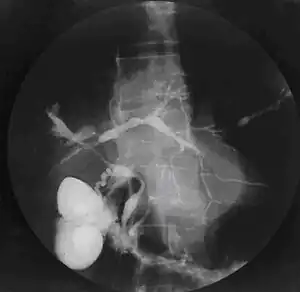

| Cholangiogram of primary sclerosing cholangitis. | |

Historically, a cholangiogram would be obtained via endoscopic retrograde cholangiopancreatography (ERCP), which typically reveals "beading" (alternating strictures and dilation) of the bile ducts inside and/or outside the liver. Currently, the preferred option for diagnostic cholangiography, given its non-invasive yet highly accurate nature, is magnetic resonance cholangiopancreatography (MRCP), a magnetic resonance imaging technique. MRCP has unique strengths, including high spatial resolution, and can even be used to visualize the biliary tract of small animal models of PSC.[18]

ERCP and specialized techniques may also be needed to help distinguish between a benign PSC stricture and a bile duct cancer (cholangiocarcinoma).[28]